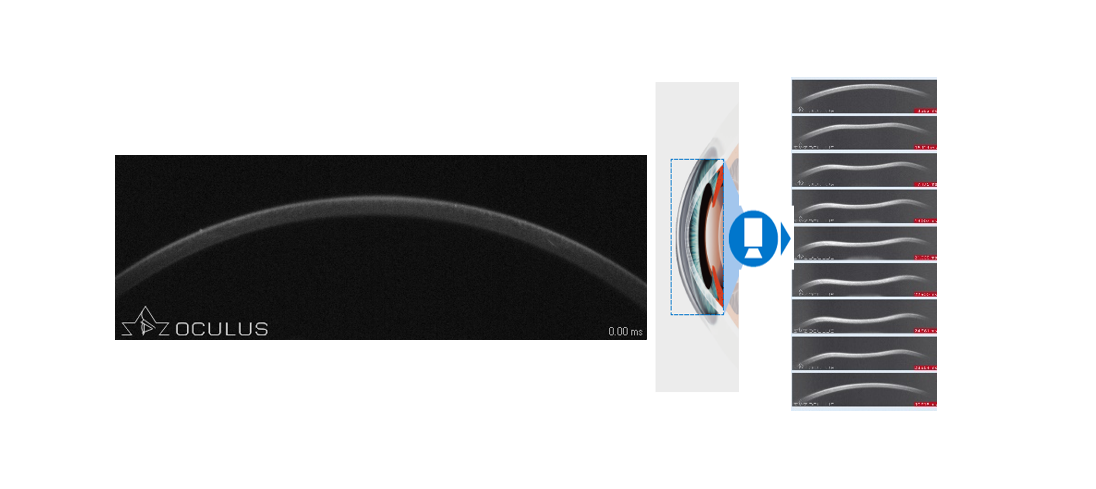

角膜生物力學檢查的作用,就是精準識別這些“隱匿性”風險。Corvis? ST采用Scheimpflug超高速相機(每秒4330幀),在31毫秒內捕捉140幅圖像,完整記錄角膜受氣流沖擊后的凹陷、變形到復原的全過程,實時分析硬度參數、生物力學校正眼壓(bIOP)等關鍵指標。結合PENTACAM的三維斷層地形圖,實現“動靜結合”的圓錐角膜篩查,極大提升了術前評估的準確性。